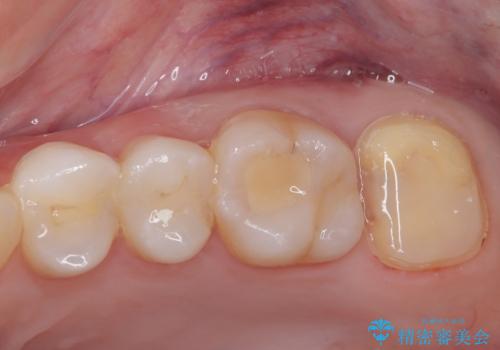

歯がしみることがなくなったと大変喜んでいただけました。

適合もよく、機能的に問題もなく、見た目も満足されていました。